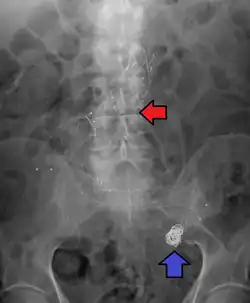

Abdominal aortic aneurysms are commonly divided according to their size and symptomatology. An aneurysm is usually defined as an outer aortic diameter over 3 cm (normal diameter of the aorta is around 2 cm),[17] or more than 50% of normal diameter that of a healthy individual of the same sex and age.[9][18] If the outer diameter exceeds 5.5 cm, the aneurysm is considered to be large.[16]

Abdominal aortic aneurysm involves a regional dilation of the aorta and is diagnosed using ultrasonography, computed tomography, or magnetic resonance imaging. A segment of the aorta that is found to be greater than 50% larger than that of a healthy individual of the same sex and age is considered aneurysmal.[9] Abdominal aneurysms are usually asymptomatic but in rare cases can cause lower back pain or lower limb ischemia.

Historically, the treatment of arterial aneurysms has been limited to either surgical intervention or watchful waiting in combination with control of blood pressure. At least, in the case of abdominal aortic aneurysm (AAA), the decision does not come without significant risk and cost, hence, there is a great interest in identifying more advanced decision-making approaches that are not solely based on the AAA diameter, but involve other geometrical and mechanical nuances such as local thickness and wall stress.[9] In recent years, endovascular or minimally invasive techniques have been developed for many types of aneurysms. Aneurysm clips are used for surgical procedure i.e. clipping of aneurysms.[40]